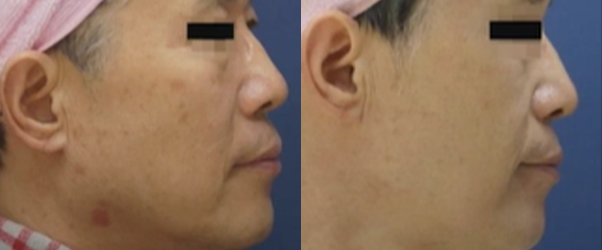

탄력 개선

탄력 개선